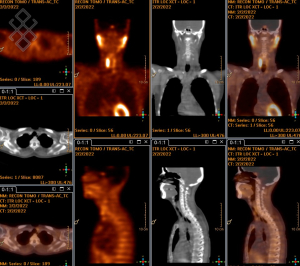

Pour l'injection du traceur radioactif (Sestamibi marqué au Tc99m), le personnel soignant vous posera un cathéter. 15 minutes après l'injection, le manipulateur fera les premières acquisitions dites "précoces" pendant environ 10 minutes. Ensuite, une seconde série d'acquisitions semblable aux images précoces sera réalisée environ 3 heures après l'injection. Une tomoscintigraphie couplée au scanner sera éventuellement réalisée pendant 20 minutes. Le temps d'attente entre les 2 séries d'acquisitions peut se faire en-dehors du service avec un retour à domicile possible ou en salle d'attente.